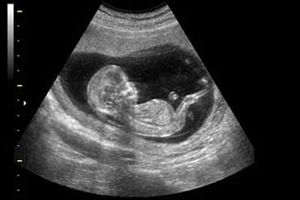

متخصص زنان و زایمان گفت: غربالگری جنین در سهماهه اول بارداری شامل یک سونوگرافی غربالگری و یک آزمایش غربالگری است که…

بسیاری از پزشکان نسبت به انجام سونوگرافیهای غیرضروری، تعدد آنها و صدمهای که این معاینهها میتوانند در ماههای مشخصی…

دبیر علمی پانزدهمین کنگره بینالمللی زنان و مامایی ایران گفت: ناهنجاریهای مادرزادی اعم از ناهنجاری قلبی، سیستم اعصاب…